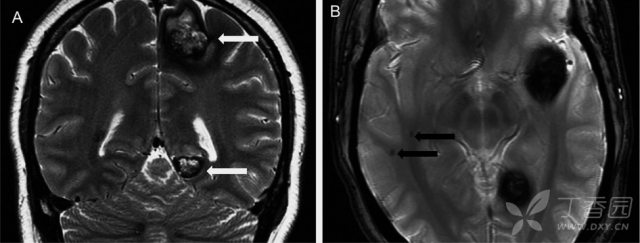

图 3:21 岁难治性癫痫伴结节性硬化症女性患者;A:FLAIR 可见高信号皮质结节伴条带状异常信号,从皮质延伸至侧脑室;B:FLAIR 可见多发高信号室管膜下结节

图 4:CT 烛泪征,即沿侧脑室的钙化灶

图 5:室管膜下巨细胞星形细胞瘤;A:T1WI;B:T1 增强

影像学上可表现为室管膜下多发结节(90%),皮质及皮质下结节(70%),脑白质异常信号和室管膜下巨细胞星形细胞瘤。室管膜下多发结节常发生于尾状核的表面,位于室管膜下,呈对称或不对称分布。T1WI 多呈等或稍高信号;T2WI 及 FLAIR 呈高信号,钙化则成低信号。增强扫描结节多强化。CT 可见典型「烛泪征」。皮质及皮质下结节 T1WI 可见结节样增厚的脑回,呈稍低信号;T2WI/FLAIR 呈高信号。增强多不强化。脑白质异常典型者可表现为「辐射带征」,即从脑室或脑室旁白质延伸至正常皮层或皮层下结节。室管膜下巨细胞星形细胞瘤为较罕见的中枢神经系统肿瘤。T1WI 呈等信号或低信号,T2WI 呈轻度至明显高信号,钙化区呈低信号。增强扫描瘤体呈明显均匀强化。可出现一侧或双侧脑室积水。